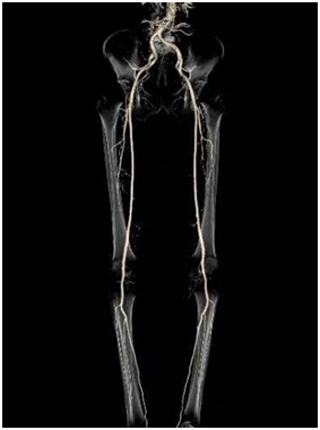

マルチスライスCT装置は、短時間で広範囲を撮影することができ、息を止めていただく時間が短いため、患者さんにとってより優しい検査が行えます。また、データ量が多く、高精細な3D画像、血管像、任意の断面像を作ることができます。

2管球CTでは、46cmの長さを1秒で撮影できる速さを持ち、息止めの困難な患者さんや、動きの速い心臓の撮影にとても強い装置です。また、低管電圧を活用して放射線被ばくを減らし、造影剤の使用量も抑えて検査することが可能となりました。

下肢血管3D画像